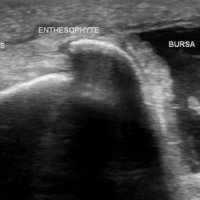

AP radiograph of the pelvis reveals extensive fluffy or "whiskering" enthesopathy of the iliac crests (red arrows), ischial tuberosities (yellow arrows), and the trochanters (black arrows). Note is also made of ossification of the iliolumbar ligament (blue arrow). Importantly, both sacroiliac joints appear normal. These findings are in keeping with diffuse idiopathic skeletal hyperostosis (DISH).

Diffuse Idiopathic skeletal hyperostosis (DISH) is a bone-forming diathesis primarily affecting the spine, with ossification of tendons and ligaments. Most of us are familiar with the spinal findings; however there are extraspinal manifestations as well such as hyperostosis at ligament attachments in the pelvis, calcaneus, tarsal bones, ulnar olecranon and patella.

Usually these are incidental findings without significant morbidity.